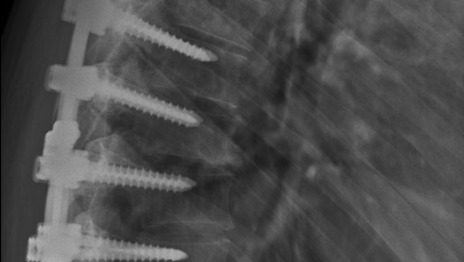

This year marks the 10th anniversary of a severe snowboarding accident that very nearly left me paralyzed. I had hit a patch of ice while on a double diamond run, lost control, went airborne as I slid off the trail, and struck a tree backwards. The impact fractured two thoracic vertebrae, fractured a rib, cracked my thorax, caused an elbow injury, and lots of internal swelling. Because of the severity of the fractures, I had to have a spinal fusion surgery to ensure the vertebrae did not damage my spinal cord, and so, for the rest of my life I will have 4 vertebrae permanently fused together with 3 titanium rods and 8 screws.